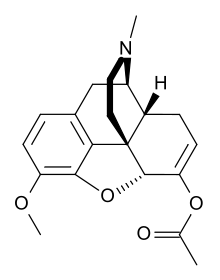

Several semi-synthetic opioids were developed in Germany in the 1910s. The first, oxymorphone, was synthesized from thebaine, an opioid alkaloid in opium poppies, in 1914.[228] Next, Martin Freund and Edmund Speyer developed oxycodone, also from thebaine, at the University of Frankfurt in 1916.[229] In 1920, hydrocodone was prepared by Carl Mannich and Helene Löwenheim, deriving it from codeine. In 1924, hydromorphone was synthesized by adding hydrogen to morphine. Etorphine was synthesized in 1960, from the oripavine in opium poppy straw. Buprenorphine was discovered in 1972.[228]

- Natural opiates: alkaloids contained in the resin of the opium poppy, primarily morphine, codeine, and thebaine, but not papaverine and noscapine which have a different mechanism of action

- Esters of morphine opiates: slightly chemically altered but more natural than the semi-synthetics, as most are morphine prodrugs, diacetylmorphine (morphine diacetate; heroin), nicomorphine (morphine dinicotinate), dipropanoylmorphine (morphine dipropionate), desomorphine, acetylpropionylmorphine, dibenzoylmorphine, diacetyldihydromorphine;[261][262]

- Semi-synthetic opioids: created from either the natural opiates or morphine esters, such as hydromorphone, hydrocodone, oxycodone, oxymorphone, ethylmorphine and buprenorphine;

Opium alkaloids and derivatives

Opium alkaloids

Phenanthrenes naturally occurring in (opium):